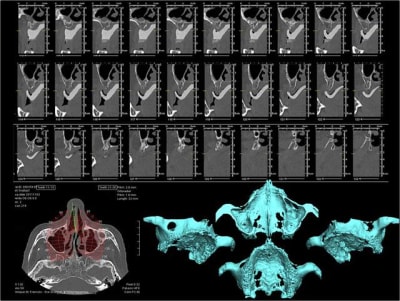

ou bien une comme ça:

--

xbk

"Si tous ceux qui croient avoir raison n'avaient pas tort, la vérité ne serait pas loin" Dac Pierre

pxav écrivait:

--------------

> ou bien une comme ça:

>

> --

ou comme ça encore...

( agénésie de 12 - expansion osseuse sur une crête fine ) agénésie...

la suite à Sallanches les 2 et 3 Février pour ceux qui veulent encore s’inscrire)

voici peut être une autre solution qui te satisfera d'avantage car beaucoup plus simple à mettre en œuvre.

c'est une simple ROG avec des vis pour maintenir l'espace sous la membrane.

oups ! j'avais oublié les opt

merci à ceux qui ont déja pratiqué cette technique de me dire quel est leur mode opératoire. les résultats, les p'tits trucs pour faire avancer la science quoi ...